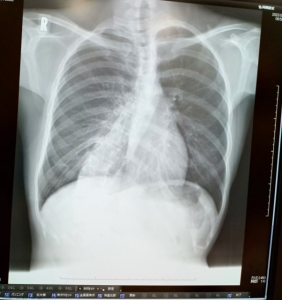

Mさん(16歳女性)の事例:30度の側弯症が17度まで矯正

今回ご紹介するMさん(16歳女性、大阪市在住)は、病院で側弯症30度と診断され、お母さんと一緒に当院に来院されました。

Mさんは病院で思春期特発性側弯症と診断されました。

側弯症の角度は30度。

施術の経過:月1回、6回の施術で角度が大幅に軽減

Mさんには、約6ヶ月の間に月1回程度、計6回通院していただきました。

施術前:側弯症の角度 30度以上

施術後:側弯症の角度 17度まで軽減

また、側弯症の重症度を評価する方法の一つに、前かがみになったときの背中のねじれ(回旋角度)を測る検査があります。

施術前:回旋角度 14~15度

施術後:回旋角度 7~8度に軽減

回旋角度が15度を超えると重症とされる中、Mさんの角度は半分近くまで軽減しました。

手術をせず、窮屈なコルセットも必要とせずに、ここまで角度を矯正できたんです。